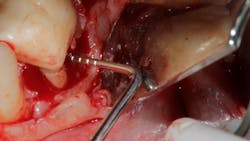

No. 2—The anatomy of the roots in the furcation are often concave and very hard to instrument, even if access to the furcation is possible (figure 4).

Technology solution: Many commercially available lasers have handpieces with tips capable of side firing and/or radial firing. This would be similar to an umbrella opening up or being in a cave and having the ability of a flashlight to completely illuminate in a 360-degree direction. In other words, the laser has the capability to penetrate all areas and convexities harboring the bacteria that is preventing proper detoxification/tissue regeneration.